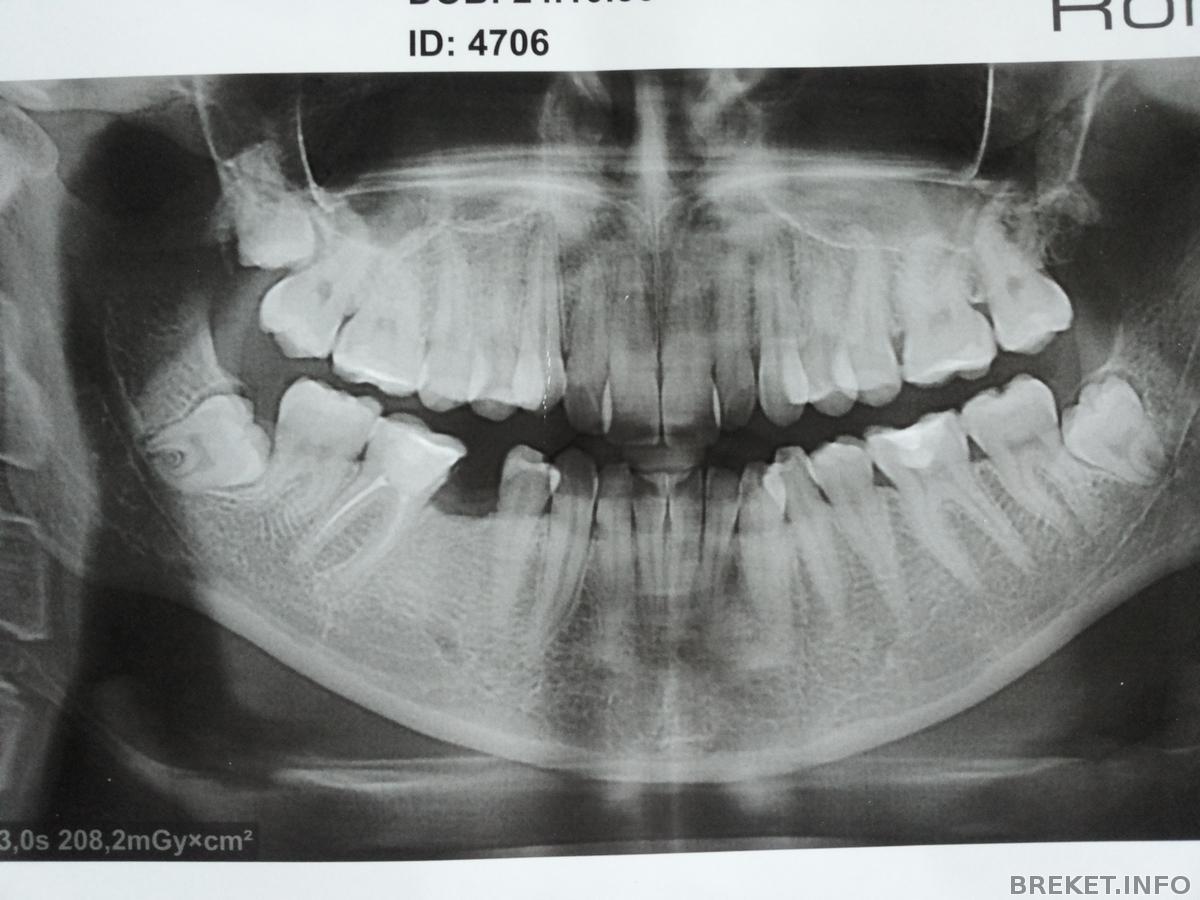

Хотела у вас всех спросить совета, у меня нет пятого зуба внизу, просто вот так нет не было зачатка коренного изначально, а еще у меня нет одной восьмерки наверху, вот такая ошибка природы, орт сказала такой часто встречается. Так вот такой вопрос, четверка уже значительно уехала, так что между ней и клыком образовывается щель, а как же шестерку и семерку к центру придвигать будут, и чтоб центр не сместился??? может у кого подобная ситуация, как с этим справляются?

У меня не выросла коренная двойка, тоже ошибка природы) Обнаружилось это перед удалением зуба. Проблему с ортом будем решать просто закрытием щели. Будет небольшая ассиметрия, но я согласна на это. Ибо иплантация или протезирование это уже отдельная очередная долгая история, которая еще неизвестно, к чему приведет.